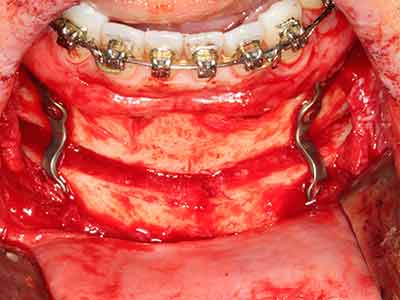

Purely orthodontic indications include orthognathic surgery, genioplasty (Fig. 27-30) and orbital decompression in patients with advanced endocrine orbitopathy as a result of Basedow’s disease (Ponto, Zwiener et al. 2014). Piezo devices are also used in maxillofacial surgery and to remove tumours at the base of the skull in various hospitals.